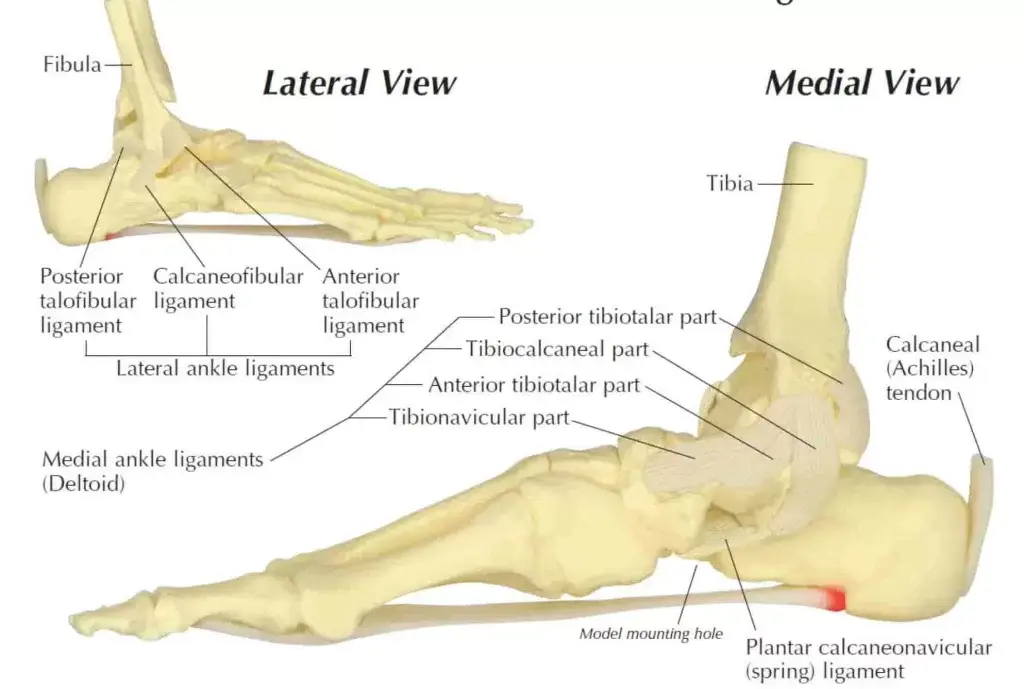

The ankle is a complex joint, with the ability to hinge up and down, turn in and out, and rotate. The ankle gains its stability from the structural arrangement of the bones, and from the ligaments that connect the bones together.

- Includes the ligaments of anterior talofibular (ATFL), posterior talofibular (PTFL) and calcaneofibular ligaments (CFL).

- Includes the deltoid ligaments, which are made up of anterior tibiotalar ligament (ATTL), posterior tibiotalar ligament (PPTL) and tibiocalcaneal ligament (TCL).